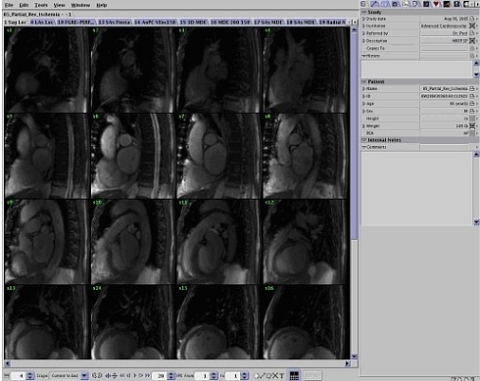

The ReportCARD 4 application is a reviewing and reporting application for Magnetic Resonance Imaging (MRI) data, in particular, Cardiac MRI. It provides simultaneous reviewing and report creation of cardiac MR exams with multiple series containing DICOM images. Multi-phase cardiac images are automatically displayed as time-lapse animations with no user interaction.

This tool is capable of automated calculation of all quantitative results derived from user measurements. It also includes automatic body surface area correction for appropriate cardiac analysis. Once the image analysis is completed, the physician can approve the report using the signature feature.